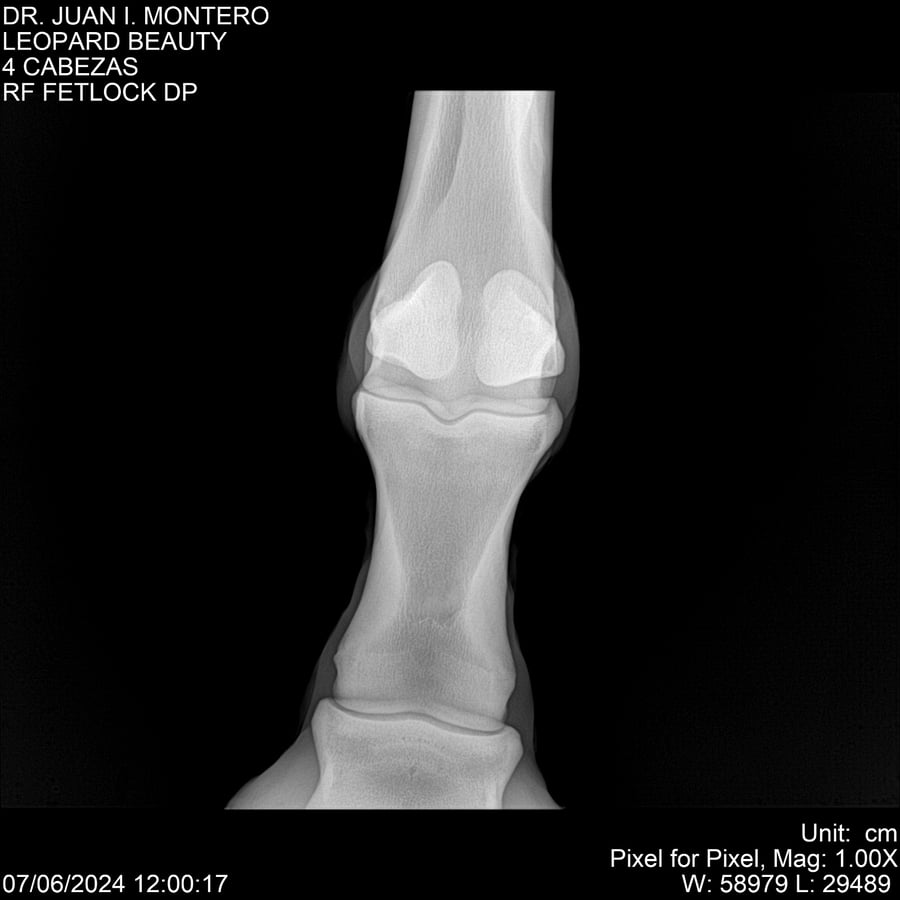

LOTE 16, LEOPARD BEAUTY Lote Anterior Volver al remate Lote Siguiente Ficha Contacto Montevideo - Ficha del Lote Identificador: #281095 Categoría: Yeguarizos Montevideo - 50 Visualizaciones ClicData Contacto Empresa: Abelenda N. R., Walter Hugo Nombre*: Teléfono* : E-mail* : Mensaje Enviar Registrese gratis Este contenido Exclusivo está disponible sólo para usuarios registrados Ingresar